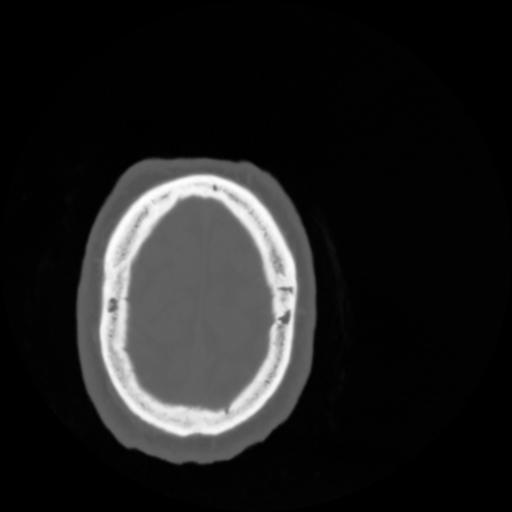

4 CEREBRO,,Vol,0.5,CEREBRO,,